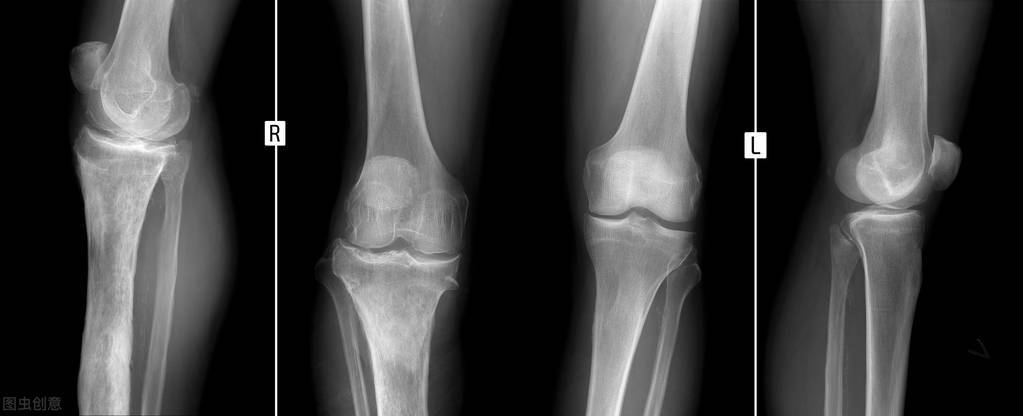

发病人群:急性骨髓炎多见小儿,任何年龄以及身体任何骨骼均可发生,易发部位为股骨下端、胫骨上端。

发病部位:好发于四肢的长干骨和长条管状的骨组织,例如锁骨、股骨、胫骨。